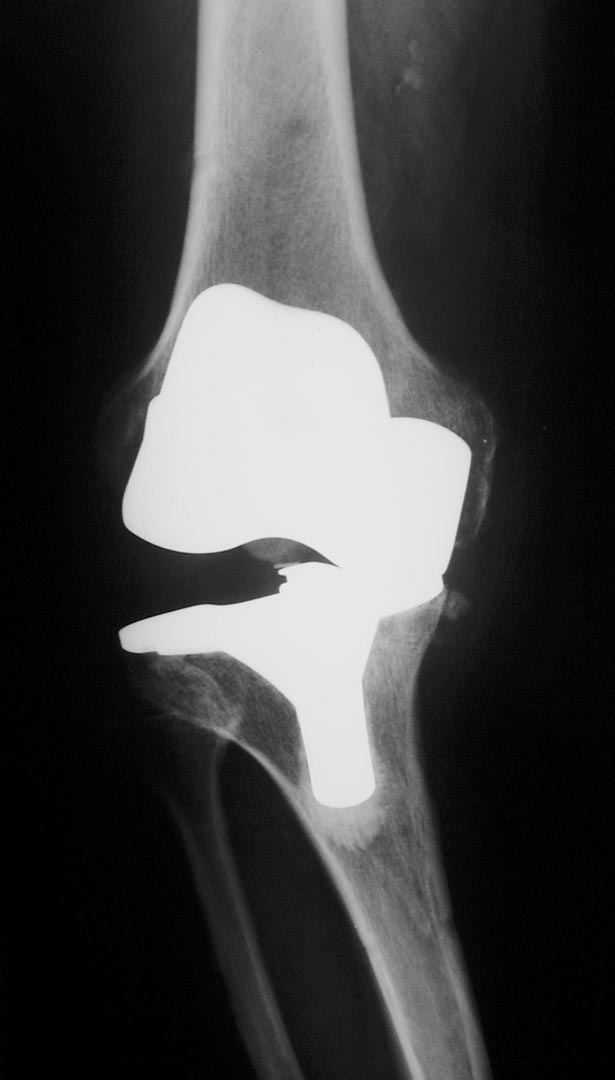

Welcher Typ einer Knieprothese für die Behandlung der Kniegelenksarthrose verwendet wird hängt neben dem Patientenalter vorwiegend davon ab, welche Teile des Gelenks abgenützt sind. So können bei isolierten Abnützungen des inneren Gelenksteils sogenannte Schlittenprothesen ( linkes Bild) und bei Abnützungen des gesamten Gelenks Totalprothesen  (mittleres Bild) eingesetzt werden: In besonders schweren Fällen von Fehlstellung in Kombination mit fehlender oder unzureichender Bandstabilität werden auch immer wieder sogenannte achsegeführte oder gekoppelte Prothesenmodelle (rechtes Bild) eingesetzt.